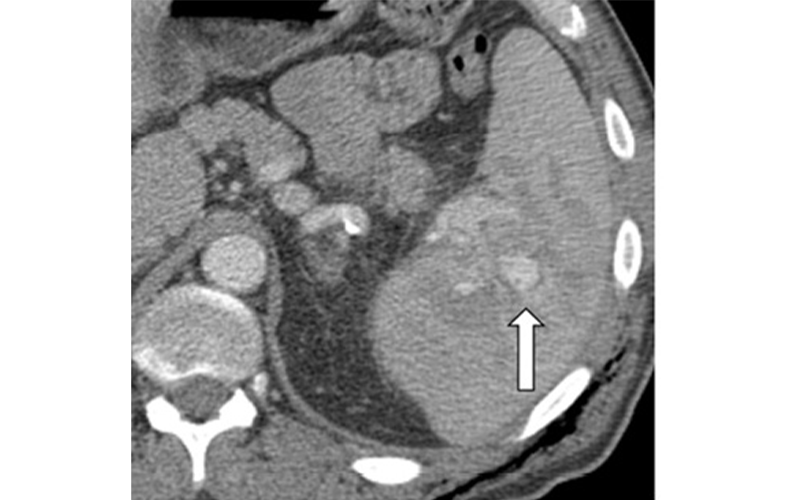

Contained vascular splenic injuries were present on 20% of blunt-trauma CT images, and active splenic hemorrage (ASH) was present on 22% of blunt-trauma CT images and was strongly associated with undergoing invasive treatment (odds ratios [ORs], 2.7 and 8.1, respectively.) Patients with ASH at CT typically had a shorter hospital stay (OR, 0.74; P<.001), possibly because of the early definitive treatment of splenic injury. Lee et al, Radiology 2021; ©RSNA 2021